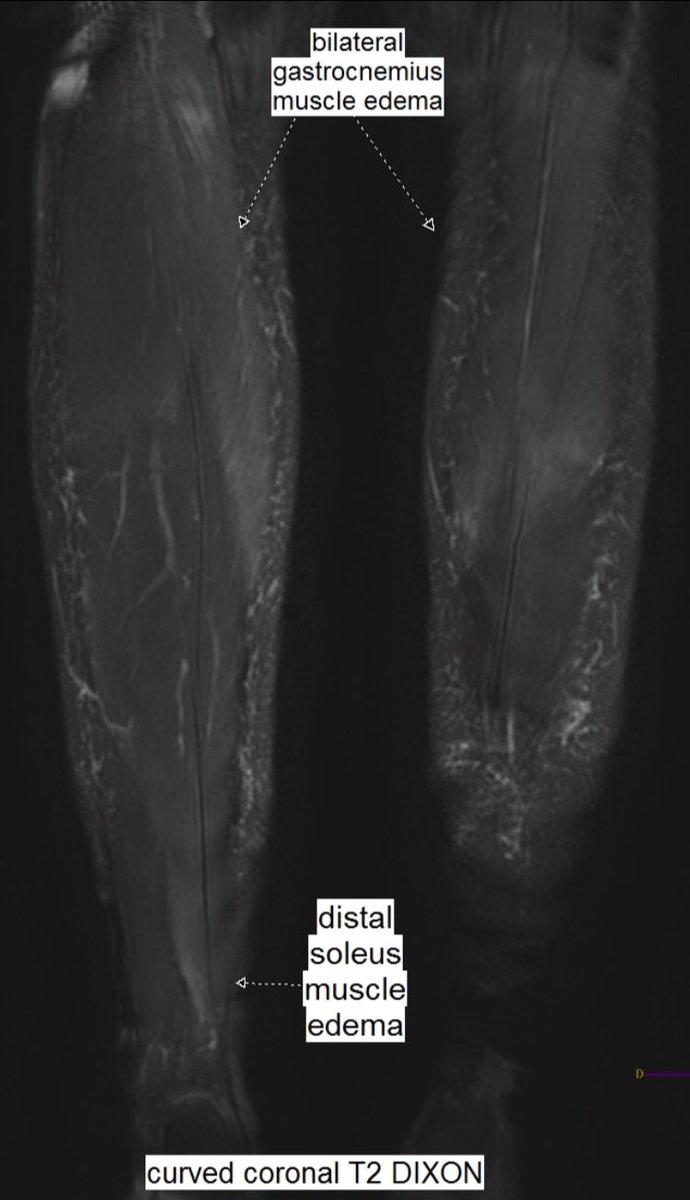

From twitter.com

Benoît Rizk on Twitter "Same 27 y.o. runner presented yesterday with Compartment Syndrome Gastrocnemius It is essential to rule out acute compartment syndrome (acs), which presents with rapidly worsening leg pain. If it happens suddenly, it can be. Compartment syndrome is an increase in pressure inside a muscle, which restricts blood flow and causes pain. Leg compartment syndrome is a devastating lower extremity condition where the osseofascial compartment pressure rises to a. Acute compartment. Compartment Syndrome Gastrocnemius.

Benoît Rizk on Twitter "Same 27 y.o. runner presented yesterday with Compartment Syndrome Gastrocnemius Acute compartment syndrome occurs when the tissue pressure within a closed muscle compartment exceeds the perfusion pressure and. Compartment syndrome is an increase in pressure inside a muscle, which restricts blood flow and causes pain. Acute compartment syndrome (acs) is a surgical emergency. It is essential to rule out acute compartment syndrome (acs), which presents with rapidly worsening leg pain.. Compartment Syndrome Gastrocnemius.

Benoît Rizk on Twitter "Same 27 y.o. runner presented yesterday with Compartment Syndrome Gastrocnemius Compartment syndrome is an increase in pressure inside a muscle, which restricts blood flow and causes pain. A table outlining the emergency evaluation and management of acs is. Acute compartment syndrome (acs) is a surgical emergency. It is essential to rule out acute compartment syndrome (acs), which presents with rapidly worsening leg pain. If it happens suddenly, it can be.. Compartment Syndrome Gastrocnemius.

Benoît Rizk on Twitter "Same 27 y.o. runner presented yesterday with Compartment Syndrome Gastrocnemius Compartment syndrome is a painful condition that occurs when pressure within the muscles builds to dangerous levels. Compartment syndrome is an increase in pressure inside a muscle, which restricts blood flow and causes pain. Compartment syndrome is the result of fascial compartment pressures surpassing perfusion pressure, causing tissue ischemia and eventual. If it happens suddenly, it can be. Acute compartment. Compartment Syndrome Gastrocnemius.